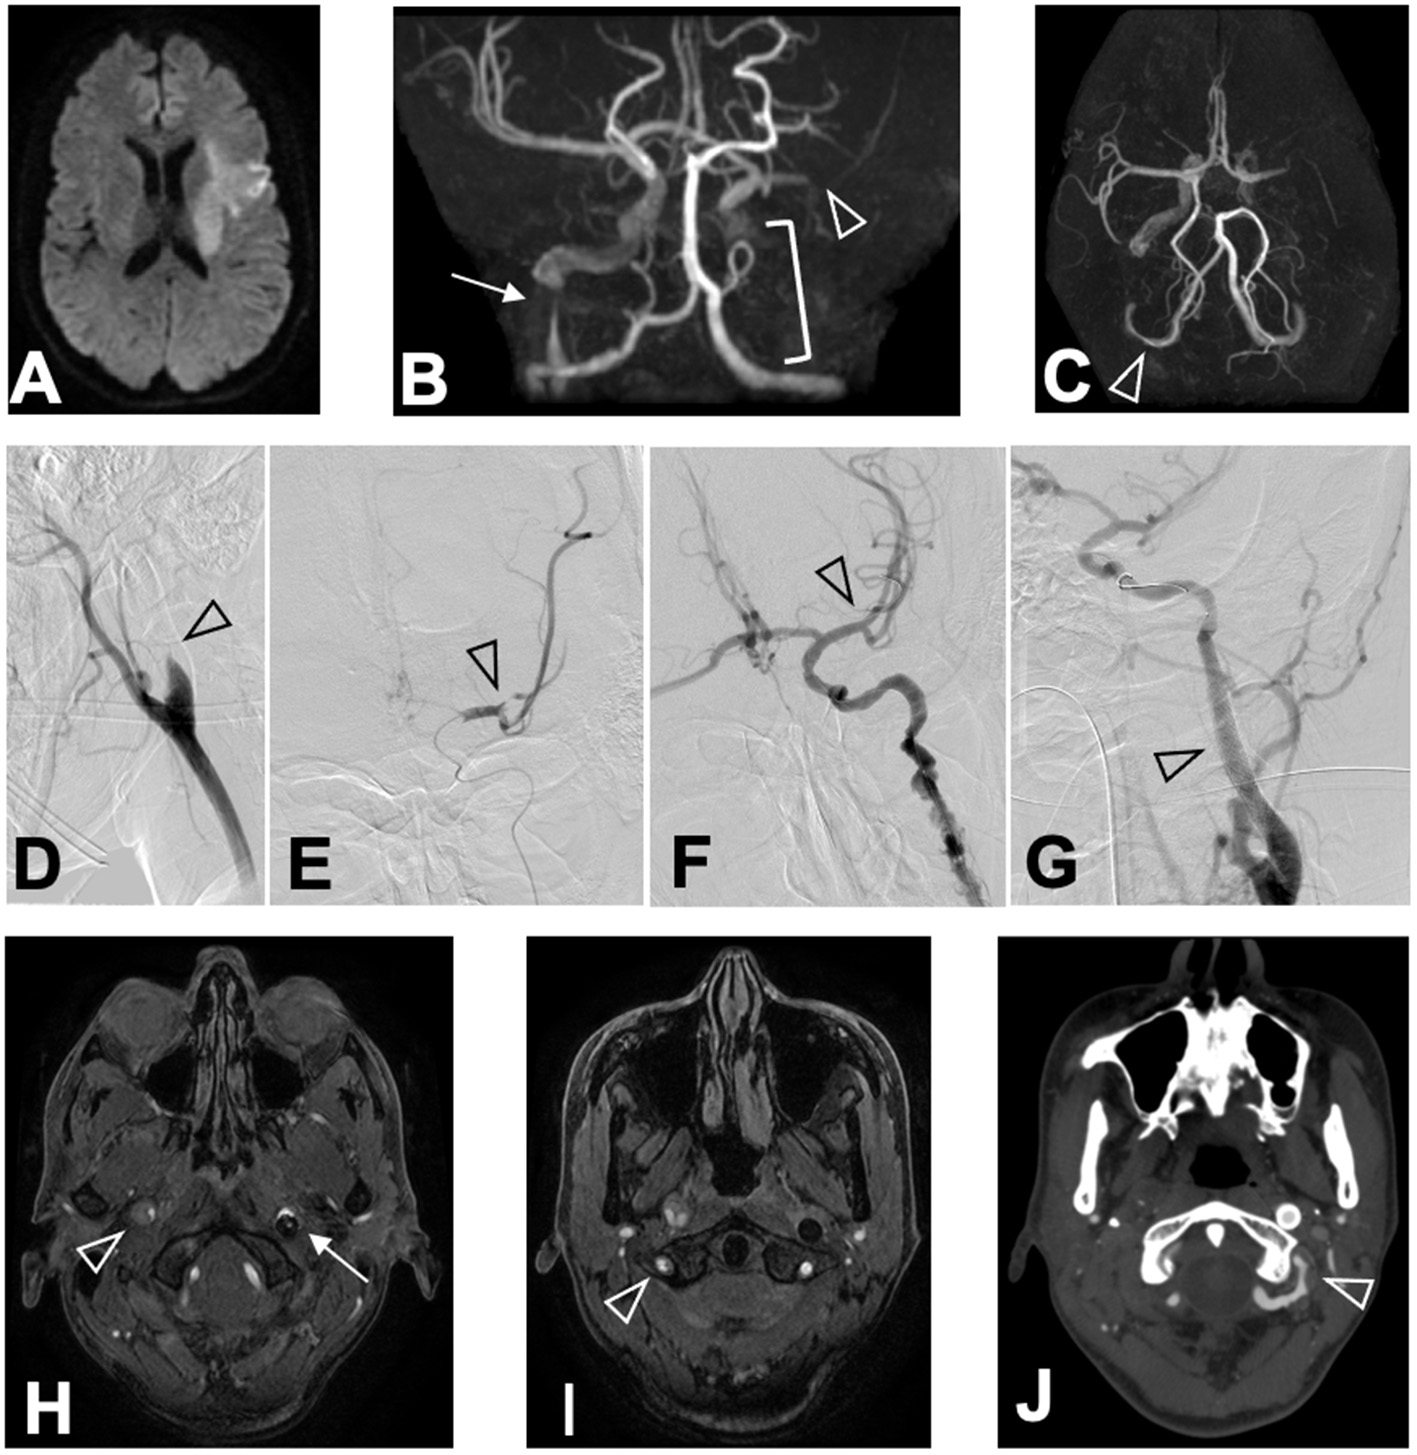

Computed tomography (CT) of the head showed no brain hemorrhage. On diffusion-weighted imaging, magnetic resonance imaging (MRI) revealed hyperintense lesions in the left frontal and temporal lobes and left corona radiata, but fluid-attenuated inversion recovery sequences showed no parenchymal hyperintensity; the Diffusion-Weighted Imaging-Alberta Stroke Program Early Computed Tomography Score was 7 (Figure 1A). Magnetic resonance angiography (MRA) and endovascular angiography revealed occlusion of the M2 segment of the left middle cerebral artery (MCA), occlusion of the left internal carotid artery (ICA), severe stenosis of the right ICA, and luminal irregularity of the right vertebral artery (VA; Figures 1B–E,H,I). Both the anterior communicating artery and the left posterior communicating artery remained patent.

Figure 1

Chronological changes of CCAD lesions. MRI (DWI) on arrival revealed (A) hyperintense lesions in the left frontal lobe, the left temporal lobe, and the left corona radiata in DWI sequence. MRA revealed (B) M2 segment occlusion of the left MCA (arrowhead), occlusion of the left ICA (bracket), and severe stenosis of the right ICA (arrow) in coronal view, and (C) luminal irregularity of the V3 segment of the right VA (arrowhead) in basal view. Angiography conducted at ED revealed (D) the left ICA occlusion (arrowhead), (E) occlusion of the M2 segment of the left MCA (arrowhead), (F) recanalized left MCA after thrombectomy (arrowhead), and (G) stented left ICA after angioplasty (arrowhead). MRA performed 24 h after hospitalization revealed (H) an intimal flap in the right ICA (arrowhead), the stented left ICA (arrow), and (I) intimal flap in the right VA (arrowhead). CTA performed 15 days after hospitalization revealed (J) luminal irregularity of the V3 segment of the left VA (arrowhead).

Administration of rt-PA was started 105 min after symptom onset, and mechanical thrombectomy via the occluded left ICA restored the left MCA perfusion to grade 3 of the Thrombolysis in Cerebral Infarction scale 185 min after symptom onset (Figure 1F). Angioplasty and stenting were performed on the left ICA to avoid re-occlusion (Figure 1G), while we conservatively observed the severe stenosis of the distal portion of the right ICA. No abnormalities were identified in the left VA at this time. Whole-body CT after rt-PA administration and thrombectomy revealed no hemorrhagic complications in the brain or the uterus.

Despite the normal appearance of the left VA on the initial investigation and CT angiography (CTA) performed 8 days after patient hospitalization, dissection of the V3 segment of the left VA with stenosis was identified by CTA 15 days after hospitalization (Figure 1J). There was no restenosis of the left ICA stent, and both the true and false lumens of the right ICA and right VA remained patent. The patient did not develop any new symptoms during this time.